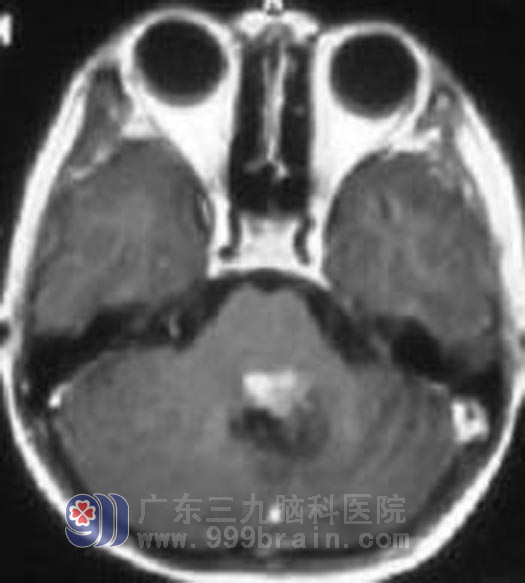

放疗后

到了2007年9月,小莹莹已经6岁了,正是幼儿园毕业准备上小学的时候,莹莹再次出现恶心呕吐,警觉的父母直接带这莹莹来到了广东三九脑科医院肿瘤综合治疗中心,查头部MR显示四脑室见明显强化灶,蔡林波主任检查此时的小莹莹除了恶心呕吐症状以外还出现了一系列的阳性体征,包括反应迟钝,双眼水平眼震,双眼外展。出现右脚跛行,这一次的肿瘤似乎比第一次来得更加凶猛。蔡林波主任结合莹莹的病史考虑小莹莹肿瘤复发可能性大,建议再次手术,术后再行放疗。父母考虑到小莹莹身体瘦小,且之前已经经历过一次手术,担心手术风险太大,遂决定不再考虑手术治疗,要求直接放疗。通过完善的检查,指定个性的治疗方案。2008年10月小莹莹接受了头部的适行调强放疗,距离第一次发病治疗正好两年。放疗结束后小莹莹恶心呕吐症状已经完全消失,复查头颅MR肿瘤较前缩小。http://www.999brain.com/

吸取了第一次的教训,放疗后父母都带着小莹莹坚持复查,每次复查都是好消息,小莹莹的脑瘤呈持续的缩小趋势,而小莹莹也没再出现过恶心呕吐,头痛头晕的症状。前日爸爸又带着小莹莹复查,结果显示她右侧肢体肌力完全恢复,双眼外展情况也较前明显好转,基本接近正常,复查头颅MR,影像检查已经看不到肿瘤痕迹。现在小莹莹正常上学,已经升三年级了。

广东三九脑科医院肿瘤综合治疗中心 蔡林波主任解析:毛细胞星形细胞瘤属良性肿瘤,其首选治疗为手术,但业内的看法不一,目前国内部分专家遵循外国文献报道,认为毛细胞星形细胞瘤术后残留无需放疗。但尽管毛细胞型星形细胞瘤为良性肿瘤,但仍有复发风险,术后加辅助放疗能及时杀灭残存肿瘤,保证了预后,即使复发后行放疗效果仍然很好。该患者目前情况良好,根据她这几年肿瘤程持续缩小的情况判断,放射线已经将肿瘤细胞杀灭,死亡的肿瘤细胞处于被分解的状态,影像学上肿瘤还将继续缩小直至消失。http://www.999brain.com/